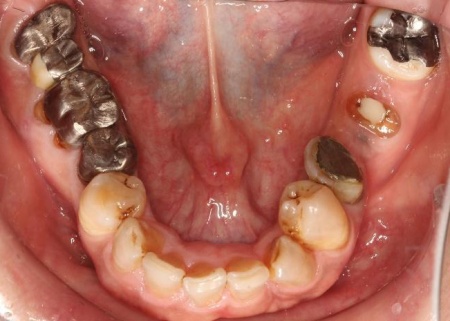

治療前

拝見したところ、もともと左上の歯と左下前歯が欠損しているうえ、奥歯の欠損も進んでいたため、噛み合わせが低くなっていました。

また、下の歯は歯根だけが残る「残根」もあり、全体的に噛み合わせが不安定です。

さらに食いしばりの習慣があることから、残っている歯や顎関節に過度な負荷がかかっていると考えられます。

このまま放置すると、食いしばりによる歯の破折や欠損の増加、顎関節への負担増大、前歯の突出の進行などのリスクがあるため、早急に治療を開始する必要があると診断しました。

下顎は残根も利用しながら、矯正用の小さなネジ「テンポラリーインプラント(インプラントアンカー)」を顎の骨に埋め込んで固定源とする方法も併用し、歯を移動させました。